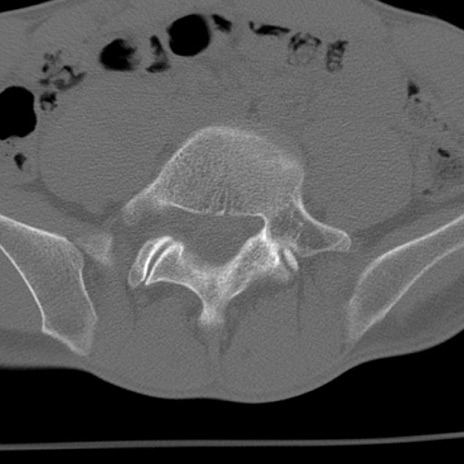

症例3 腰椎CT(横断像)

腰椎CT